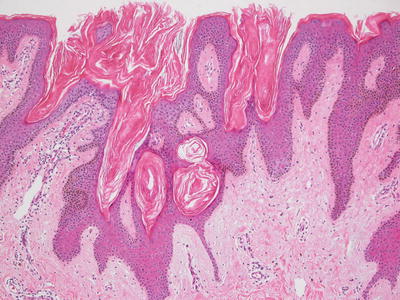

23.16.2 Histology

There are several different histologic patterns that can be seen in these hamartomatous lesions. The histologic changes include hyperkeratosis and acanthotic epidermis (Figs. 23.28, 23.29 and 23.30). Hypergranulosis is seen in some cases, but it is not pronounced. The rete ridges are elongated. Cytologic atypia is not present, and mitotic activity is not increased.

Fig. 23.28

An epidermal nevus has a papillomatous surface and acanthotic epidermis that is histologically indistinguishable from a seborrheic keratosis

Fig. 23.29

The epidermis is comprised of basaloid cells with focal horn cysts and overlying hyperkeratosis in epidermal nevus

Fig. 23.30

In some cases, changes of epidermolytic hyperkeratosis are seen in an epidermal nevus